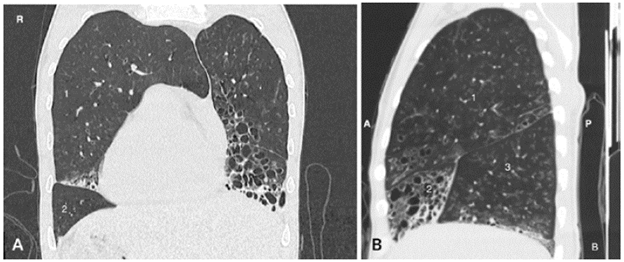

Symptomatology was interpreted as an infectious picture of low respiratory tract origin and possible bacterial sinusitis, for which antibiotic management was initiated with ampicillin sulbactam. Further paraclinical tests included a chest x-ray that showed dextrocardia, with no signs of consolidation or pleural effusion. This was complemented with high-resolution computed tomography (HRCT) (Figures 1 and 2) and a computed tomography (CT) of the paranasal sinuses (Figure 3).

After finding dextrocardia, it was necessary to ascertain visceral situs (normal, inverted, ambiguous). A simple tomography documented pulmonary bronchiectasis, as well as liver on the left side (Figure 4), leading to suspect KS; this was confirmed with findings of chronic sinusitis in paranasal sinus tomography. In addition, HRCT showed tomographic signs of infectious bronchiolitis.

Imaging plays a key role in proving the anatomical findings that support KS. However, the diagnostic precision of PKD is achieved with the elements mentioned above, all of which are difficult to access. Inadequate sweeping of pulmonary secretions causes bronchial dilatations or bronchiectasis that are observed as tubular opacities or ovoids of variable sizes in chest x-ray, a less sensitive method for its detection with respect to HRCT. 12

On the other hand, thin-section chest CT is the gold standard to detect bronchiectasis, although thick-section CT can also be used. The bronchial artery index is used to identify it and should normally be close to 1; however, it may increase during vasoconstriction or be normal during pulmonary hypertension. Therefore, the cardinal sign of bronchiectasis on a CT scan is the observation of bronchioles less than 1 cm from the pleural silhouette (Table 2). 12

According to the classification proposed by Reid 15, bronchiectasis is divided into cystic, cylindrical and varicose. Its characterization, in the case of this patient, was carried out by means of a CT scan that showed a predominantly cystic pattern. According to another case report 16, the three types of bronchiectasis have been described in patients with KS in equal proportions.